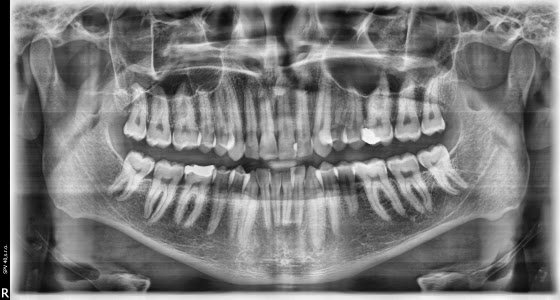

RTG Zubné – Spišská Nová Ves, Poliklinika pri Hornáde, O.S.C. s.r.o.

Na našej prevádzke poskytujeme zubné panoramatické RTG /OPG snímok/